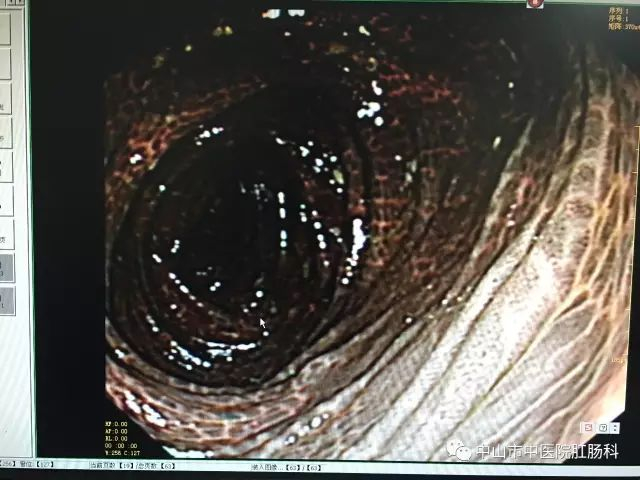

医生说,这样的肠粘膜改变,称之为“大肠黑变病”,在日常检查过程中检出率不低,但是像这位患者这样黑的,实属罕见。而正常的肠子,是粉红粉红、血管纹理分明的,如下图:

大肠黑变病

镜下表现为结肠黏膜光滑、完整,可见浅棕色、棕褐色或黑色的色素沉着,呈条纹状、斑片状、虎皮状改变,可网络状间断或连续分布,肠腔明显变暗。